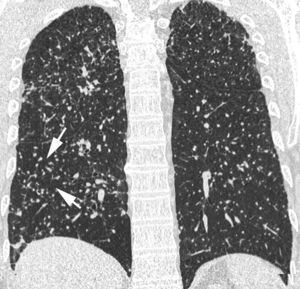

Los hallazgos radiológicos más frecuentes de la NIU incluyen la disminución global del volumen pulmonar, la presencia de opacidades pulmonares de tipo reticular y de localización basal y periférica, y la existencia de panalización (fig. 7)11,18. La presencia exclusiva de un patrón en «vidrio deslustrado» es un hallazgo TCAR infrecuente en la NIU. La gran utilidad de la TCAR en los pacientes con NIU reside en mostrar el grado de fibrosis y establecer la fase evolutiva de la enfermedad. Dado que la FPI es una enfermedad de difícil tratamiento que tiene un mal pronóstico, en los casos con panalización evidente y criterios característicos en la TCAR no debe realizarse biopsia pulmonar5.